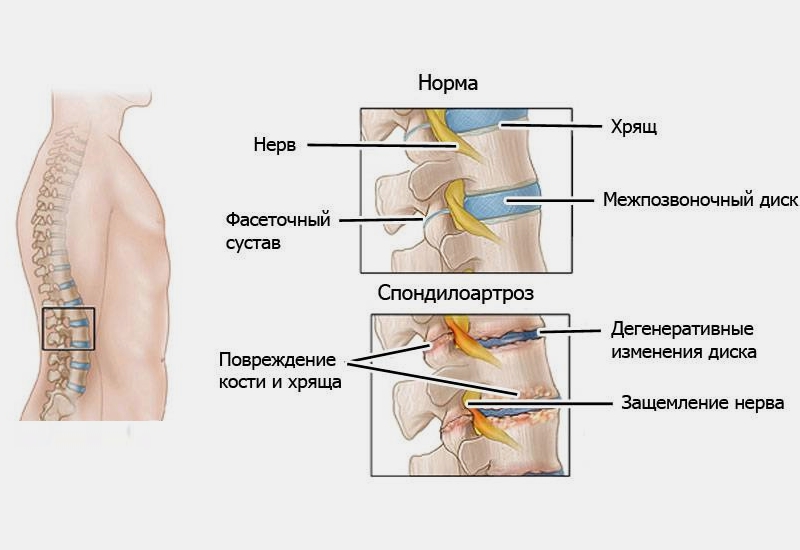

Остеоартрит фасеточных суставов: медицинские снимки и схемы